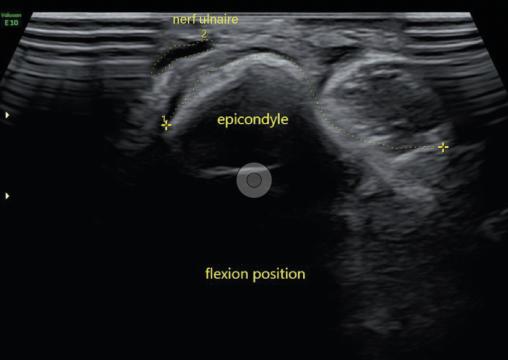

Deux ans après le premier épisode, il reconsulte pour le même motif. Un nouvel EMG révèle un ralentissement de la vitesse de conduction du nerf ulnaire droit au niveau du coude. Une échographie dynamique du coude met en évidence un gonflement fusiforme du nerf ulnaire dans la gouttière cubitale ainsi qu’une luxation du nerf ulnaire au-delà de la tubérosité condylienne lors de la flexion de l’avant-bras sur le bras (fig. 1 et 2). Une transposition cubitale est effectuée (fig. 3) permettant la disparition des symptômes en quelques semaines.

Le diagnostic est posé après réalisation d’une échographie dynamique en flexion et en extension montrant la luxation du nerf ulnaire à la flexion. L’électromyogramme est, quant à lui, moins sensible, pouvant objectiver un bloc de conduction cubital et un ralentissement de la vitesse de conduction au niveau du coude.